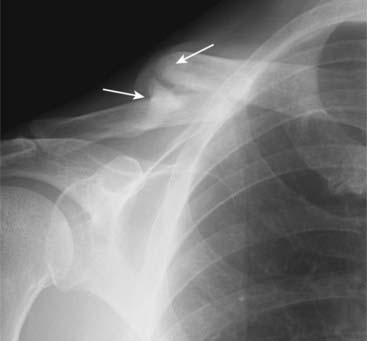

image Posterior dislocation of the shoulder (uncommon)

The humeral head is fixed in internal rotation and looks like a “lightbulb” in all views of the shoulder. Look at a view like the axillary or “Y” view to see if head still lies within the glenoid fossa. On the “Y” view (an oblique view of the shoulder), the head will lie lateral to the glenoid in a posterior dislocation (Fig. 22-29).

Figure 22-29 Posterior dislocation of the shoulder.

Posterior dislocations of the shoulder are much less common than anterior dislocations but more difficult to diagnose. A, On the frontal view, look for the humeral head (H) to be persistently fixed in internal rotation and resemble a “lightbulb” no matter how the patient turns the forearm. There is also an increased distance between the head and the glenoid (solid black arrow). B, On the “Y” view, the head (H) will lie under the acromion (A), a posterior structure of the scapula. The coracoid process (C) is anterior. Normally, the head is centered between the coracoid and the acromion in the glenoid fossa (G).